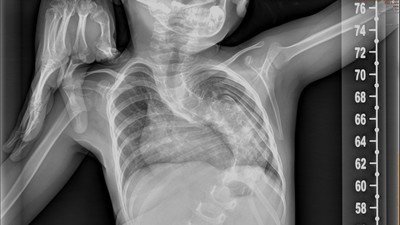

Tengo una hija de 4 aňos que estaba tratándose de una enfermedad llamada escoliosis congénita agresiva ,en el hospital VIRGEN DEL ROCÍO DE SEVILLA y a la espera de una delicada operación de la cual sólo hay un cirujano con su equipo médico en espaňa que está en este hospital mencionado antes y en el cual ya no vamos a tener.Se quedan cerca de 20 niňos y familias desolados y sin ayuda .NECESITAMOS UN CAMBIO EN LA SANIDAD Y QUE NO NOS ABANDONEN.